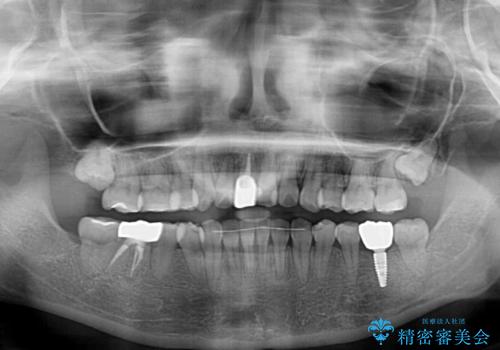

矯正治療を行う前に、根管治療の必要な上顎前歯と下顎大臼歯の根管治療を行い、矯正治療の途中で下顎の欠損部にインプラント埋入することとし、矯正治療後に補綴治療を行うこととしました。

矯正治療中にインプラント埋入を行うなど、余計な時間や無駄のない治療を行うことができました。